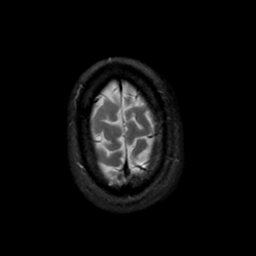

MR Study #19, August 25, 1991 -- Slice #45

[Home][Help][Clinical][Tour 1][Tour 2] Slice 45